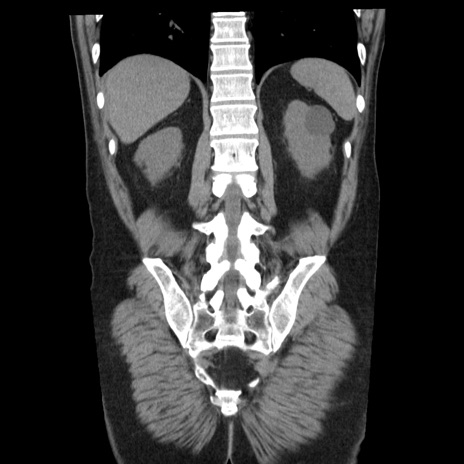

症例29(冠状断像)

【症例】40歳代男性

【現病歴】2日前から胃痛あり。徐々に周期的な激痛に変化した。本日になっても激痛があるため受診。

【身体所見】意識清明、BT 38-39℃台あり、腹部:膨満、やや硬、右下腹部に圧痛あり。

【データ】WBC 8500、CRP 23.26